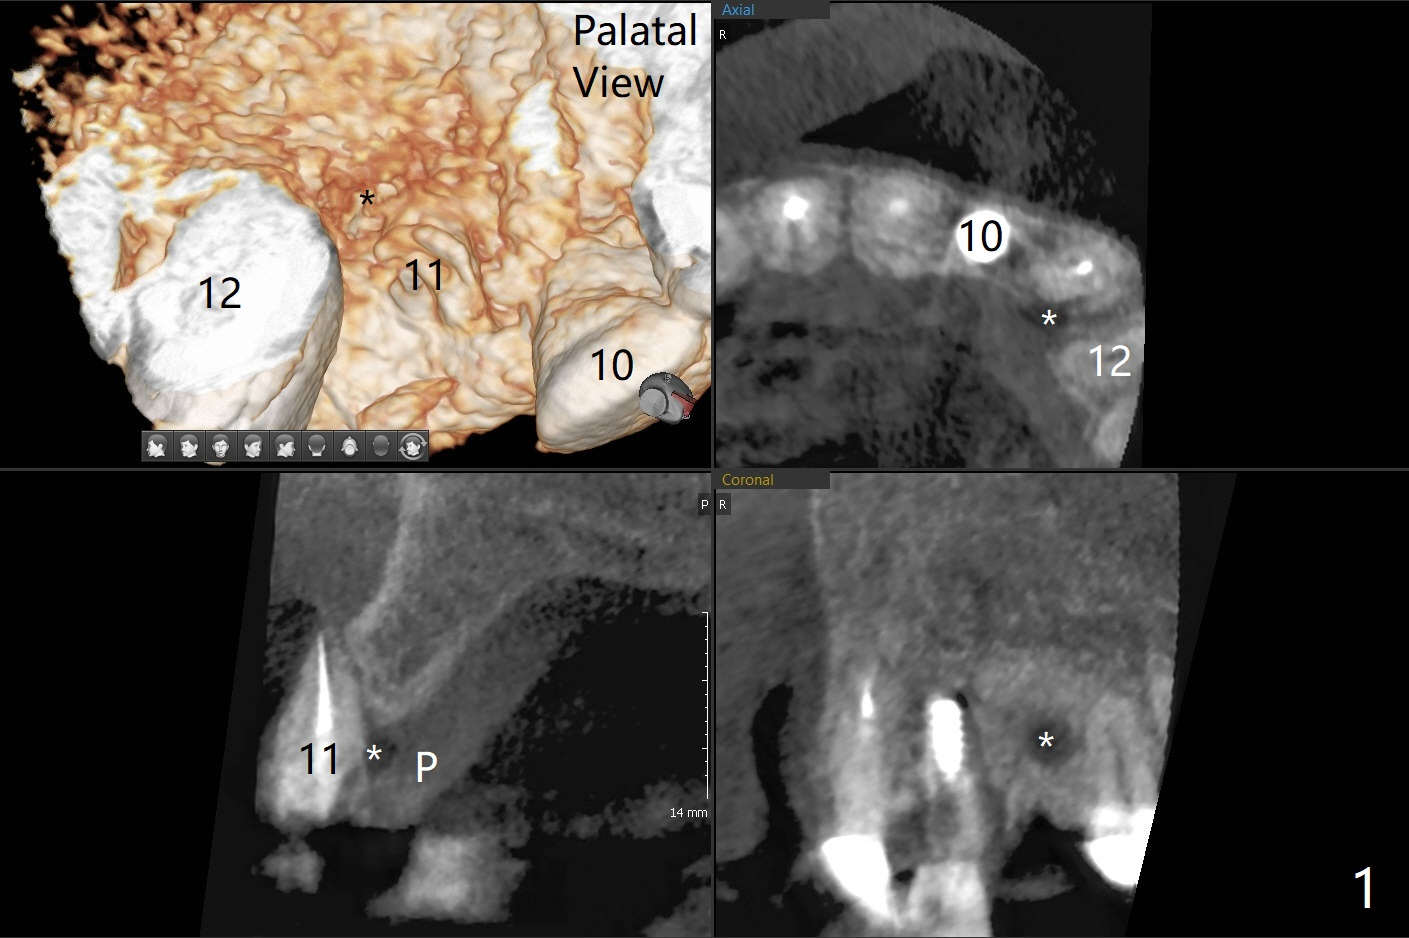

左上尖牙拔除前发现远中腭侧瘘道,拔除后发现相对牙槽嵴骨缺损(图一(术前CT):*),其实患牙根尖在颊侧骨板颊侧(图二:>),拔除后,根尖骨板缺损(图三:>),由于后者离颊侧牙槽嵴(图四:红箭头)远,骨粉修复重要性不如腭侧牙槽嵴(图四:白箭头),当窄植体植入后(图四:绿色),首先在腭侧植骨(图五:红圆圈),因为基台放置后(图六:粉红色),腭侧植骨开口狭窄(图六:白箭头)。即刻种植总是腭侧,颊侧间隙大,颊侧根尖缺损填骨应该容易(图七:橘黄色圆圈),即使不全(*),无关大局。徒手初步钻洞(图八),种植(图九)方向尚可,植骨好像完全(图十:*)。术后一周临时牙冠(11,尖牙)比侧切牙还短(图十一),随着愈合,尖牙牙冠会比双尖牙还短,因为植体偏腭侧,可能需要调整临时牙冠边缘。颊侧牙龈单纯疱疹感染,颊侧根尖仍有疼痛,腭侧瘘道缩小。